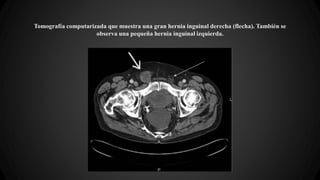

Tomografía computarizada que muestra una gran hernia inguinal derecha (flecha). También se

observa una pequeña hernia inguinal izquierda.